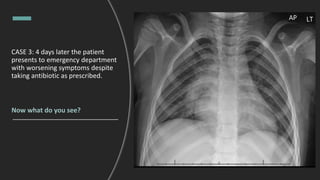

CASE 3: 4 days later the patient

presents to emergency department

with worsening symptoms despite

taking antibiotic as prescribed.

Now what do you see?

CASE 3: 4 days later patient

Impression: Focal consolidation in

medial right lower lobe (arrows)

with central lucency (stars)

compatible with cavitation

Differential: Complicated

pneumonia, tuberculosis, fungal

infection